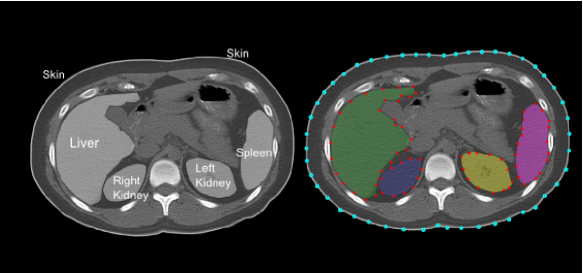

Figure 2 shows multi-object 3D ASMs for abdominal organs. Note that skins are also considered in the MA𝑀𝐴MAs to restrict the search space. Note also that mean shapes of the objects do not have any overlapped region with other mean shapes of the objects. Because, in training part, we select the objects Oisubscript𝑂𝑖O_{i} such that (OiOj)(ij)1,,M=subscriptsubscript𝑂𝑖subscript𝑂𝑗𝑖𝑗1𝑀(O_{i}\cap O_{j})_{(i\neq j)\in 1,\ldots,M}=\emptyset, implying that there is no overlaps across the objects. This fact leads to (𝐱¯𝐢𝐱¯𝐣)(ij)1,,M=subscriptsubscript¯𝐱𝐢subscript¯𝐱𝐣𝑖𝑗1𝑀(\mathbf{\overline{x}_{i}}\cap\mathbf{\overline{x}_{j}})_{(i\neq j)\in 1,\ldots,M}=\emptyset, as each mean shape 𝐱¯𝐢subscript¯𝐱𝐢\mathbf{\overline{x}_{i}} is created independently and alignment of the shapes of objects does not affect the distribution of objects in the mean shape due to the nature of the 7-parameter affine transformation A𝐴A: (OiOj)(ij)1,,M=(A(Oi)A(Oj))(ij)1,,M=(A(𝐱¯𝐢)A(𝐱¯𝐣))(ij)1,,M=subscriptsubscript𝑂𝑖subscript𝑂𝑗𝑖𝑗1𝑀subscript𝐴subscript𝑂𝑖𝐴subscript𝑂𝑗𝑖𝑗1𝑀subscript𝐴subscript¯𝐱𝐢𝐴subscript¯𝐱𝐣𝑖𝑗1𝑀(O_{i}\cap O_{j})_{(i\neq j)\in 1,\ldots,M}=\emptyset\Leftrightarrow(A(O_{i})\cap A(O_{j}))_{(i\neq j)\in 1,\ldots,M}=\emptyset\Leftrightarrow(A(\mathbf{\overline{x}_{i}})\cap A(\mathbf{\overline{x}_{j}}))_{(i\neq j)\in 1,\ldots,M}=\emptyset. Objects are not aligned individually, hence, their spatial relations before and after alignment does not change.

Refer to caption Refer to caption

Figure 2. Mean shape is generated using 3D ASM for multiple objects of abdominal region. Left: Figure includes mean shapes of liver, spleen, right and left kidneys. Right: Figure includes mean shape of skin boundary of the abdominal region as well.